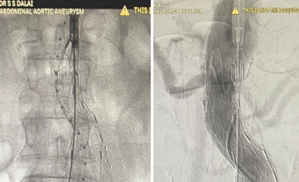

The Abdominal Aortic Aneurysm (AAA) was extending from the infra-renal aorta to both Common iliac arteries. Endovascular Aneurysm Repair (EVAR) was planned. Generally, an EVAR is done by surgically exposing femoral arteries bilaterally to take the grafts inside the aorta for Endovascular repair. We did the EVAR completely percutaneous- avoiding any surgical exposure. No Groin Cut, No surgical femoral artery exposure # SIMPLY Percutaneous. The patient Got discharged in 48 Hrs. It’s actually technically challenging to create 2 X two sets of pre-close sutures / Bilateral femoral for 20F (6mm) holes on Common femoral arteries. The procedure was done with suture closure of Bilateral 6 mm holes over the femoral without exposing the femoral - that’s the beauty.

suture-less-endovascular-aneurysm-repair-for-abdominal-aortic-aneurysm-1